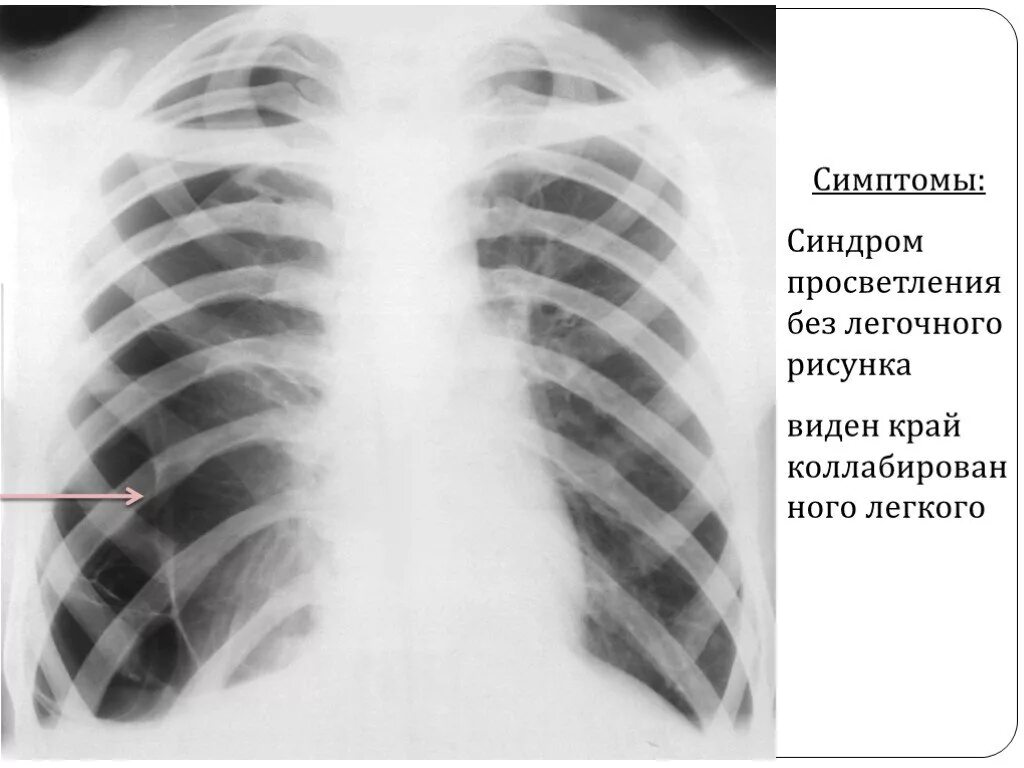

Коллабирование это